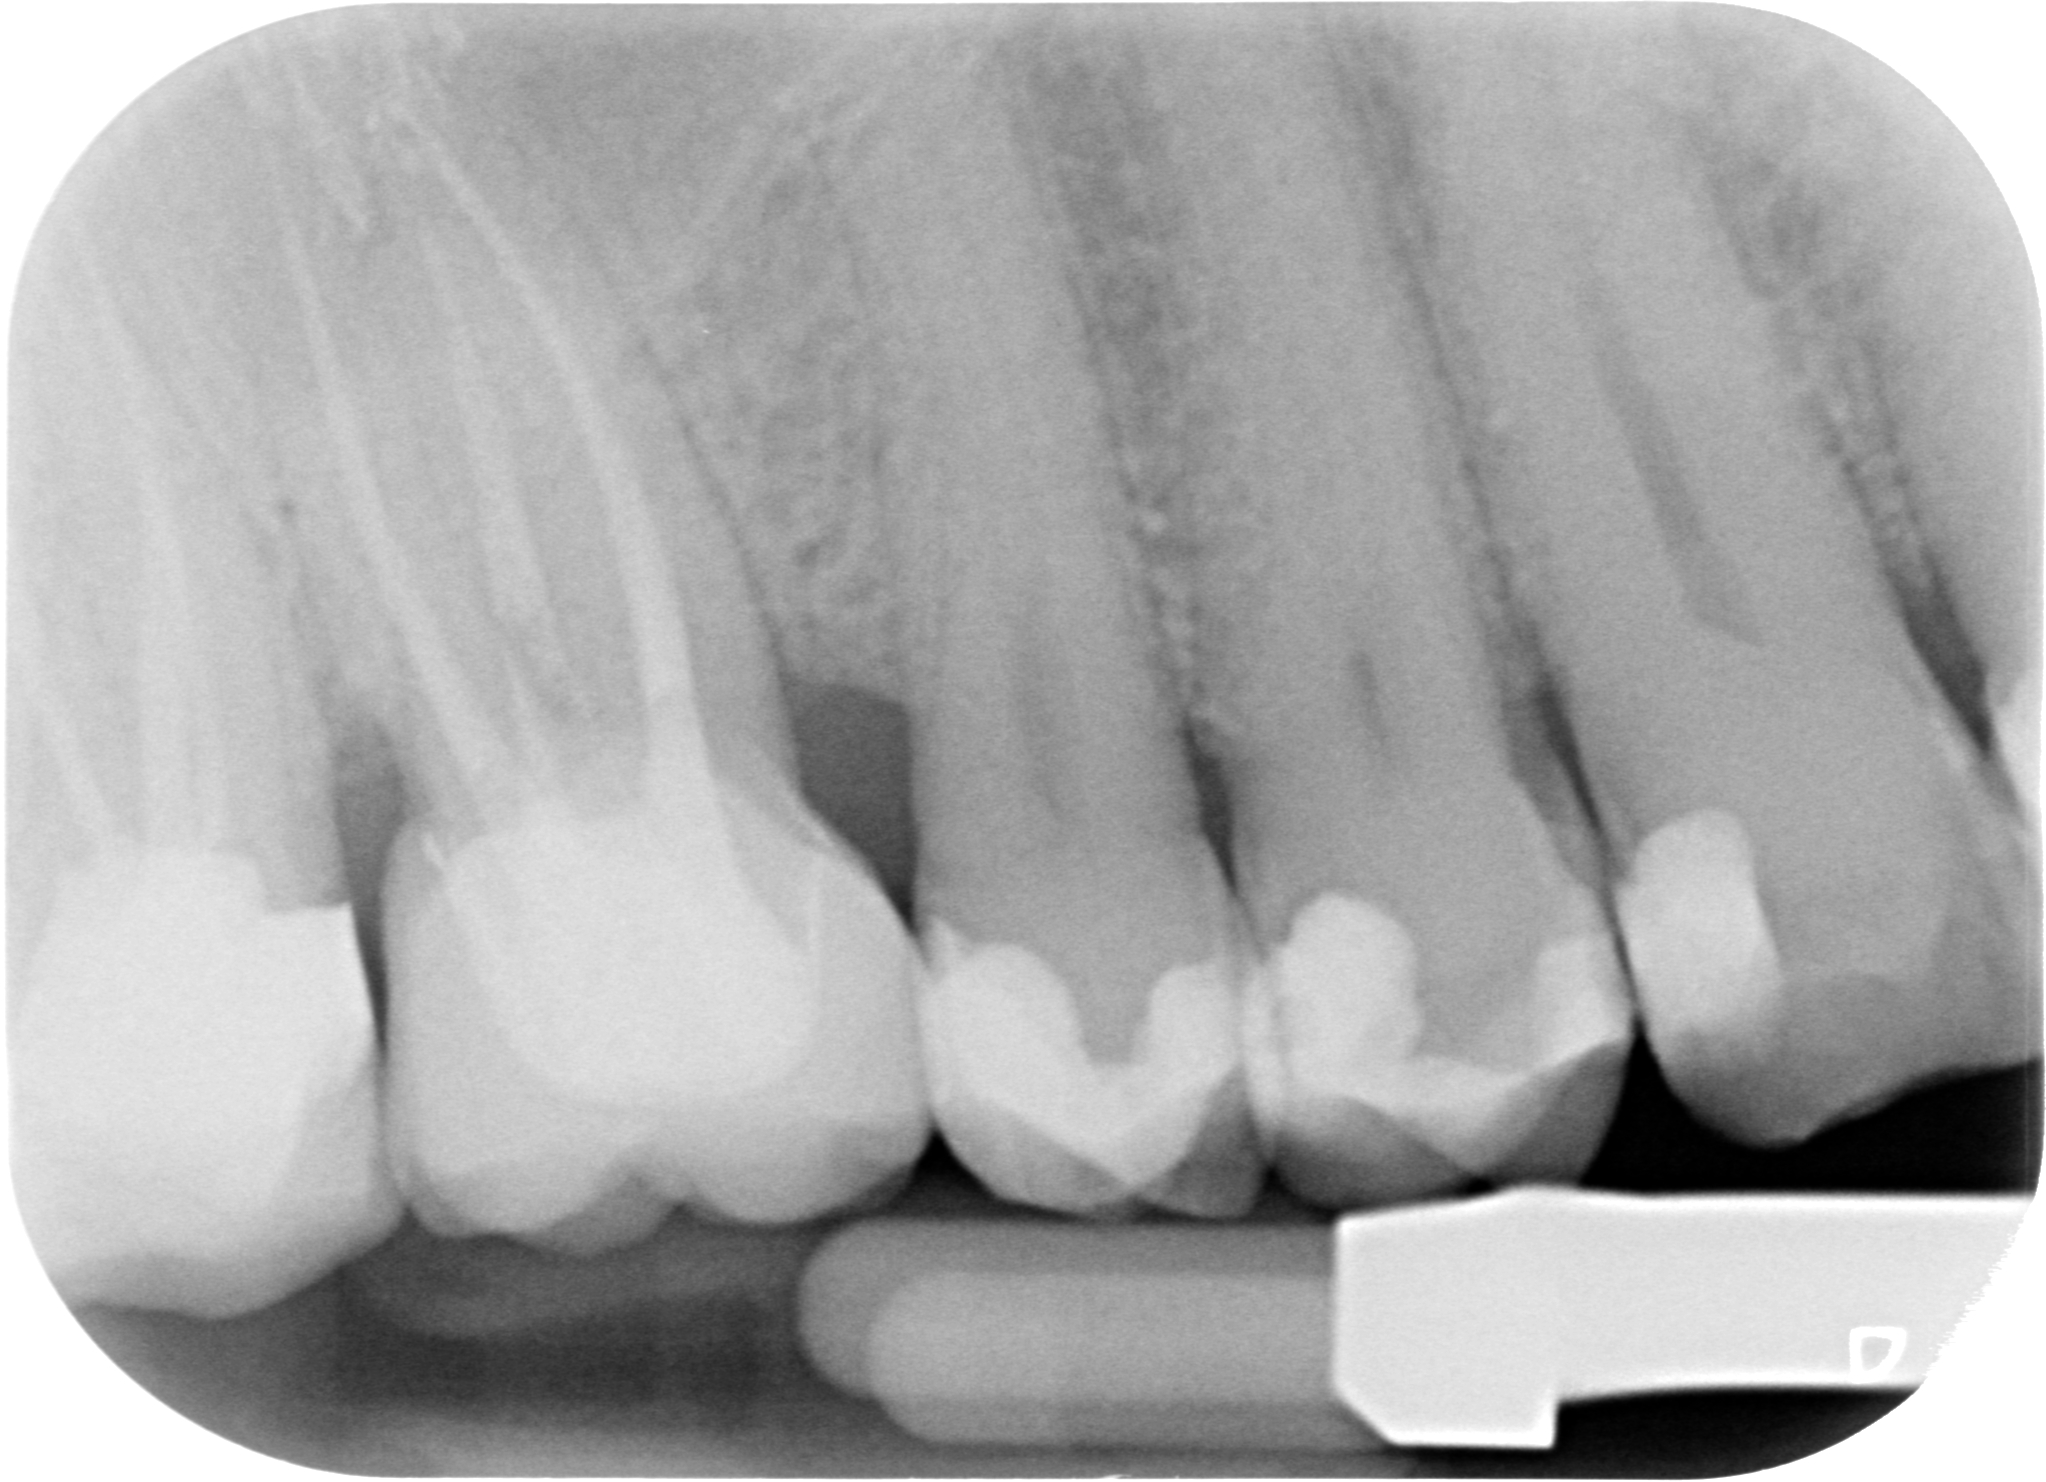

Allungamento di corona clinica 001

Accademicamente potremmo dire: CARIE SECONDARIA A CARICO DI 1.6 PRECEDENTEMENTE RESTAURATO MEDIANTE CORONA IN METALLO CERAMICA.

Ma io nella mia testa dico “chi ha fatto quella corona avrebbe dovuto fare un allungamento di corona clinica, ma non lo sapeva o non lo voleva fare. Quindi non ha potuto gestire correttamente il margine di chiusura distale. Quindi è rimasto del tessuto cariato o non è stato effettuato un corretto sigillo marginale per cui… E’ SUCCESSO IL FATTACCIO!”

Anche se il paziente non avvertiva nessun fastidio abbiamo fatto una visita completa,                che comprende le due bite-wings posteriori e ci siamo accorti del problema. Ora però lo dobbiamo risolvere. Abbiamo tre strade: